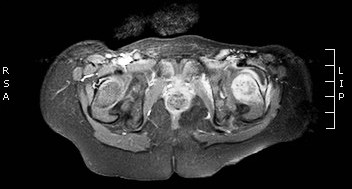

26. MRI examination, axial T2 weighted image. Irregular, large solid, inhomogeneous retroperitoneal tumor is seen. Neuroblastoma. (with the courtesy of Dr. Gábor Rudas)